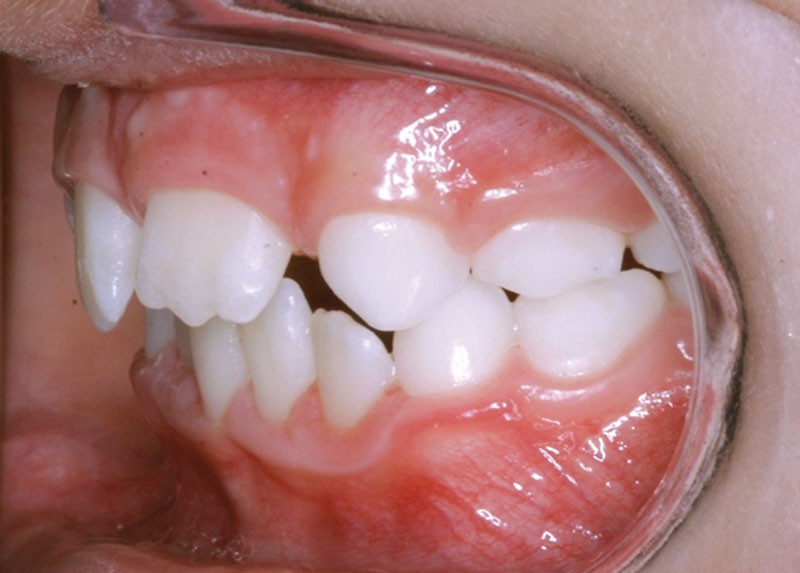

Les vues endo-buccales après extraction de 52 montrent des relations occlusales de classe II, un léger encombrement incisif mandibulaire et une tendance à la fermeture spontanée des espaces des incisives latérales confirmant le choix thérapeutique d’une fermeture d’espace (fig. 2).